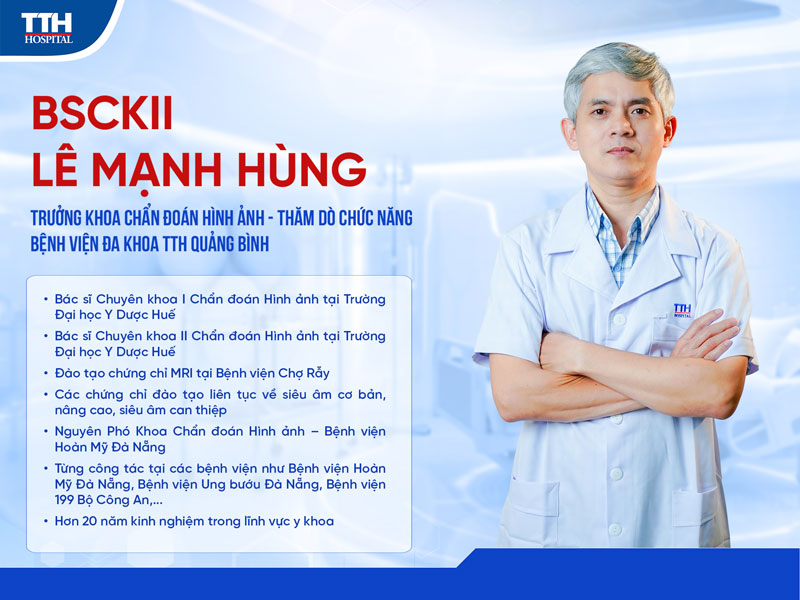

BSCKII LÊ MẠNH HÙNG - CHUYÊN GIA CHẨN ĐOÁN HÌNH ẢNH HƠN 20 NĂM KINH NGHIỆM

BSCKII LÊ MẠNH HÙNG - CHUYÊN GIA CHẨN ĐOÁN HÌNH ẢNH HƠN 20 NĂM KINH NGHIỆM

Trong y học hiện đại, chẩn đoán hình ảnh giữ vai trò quan trọng giúp phát hiện sớm bệnh lý, hỗ trợ bác sĩ đưa ra hướng điều trị chính xác và kịp thời. Tại Bệnh viện Đa khoa TTH Quảng Bình, BSCKII Lê Mạnh Hùng - Trưởng khoa Chẩn đoán hình ảnh - Thăm dò chức năng là một trong những bác sĩ có nhiều kinh nghiệm chuyên môn, đã có hơn 20 năm gắn bó với lĩnh vực chẩn đoán hình ảnh.

Với quá trình đào tạo bài bản, kinh nghiệm công tác tại nhiều bệnh viện lớn cùng tinh thần tận tâm với người bệnh, bác sĩ Lê Mạnh Hùng đã và đang góp phần quan trọng trong việc nâng cao chất lượng chẩn đoán và hiệu quả điều trị tại bệnh viện.

Để trở thành bác sĩ chuyên khoa chẩn đoán hình ảnh, BSCKII Lê Mạnh Hùng đã trải qua quá trình học tập và đào tạo chuyên môn nghiêm túc tại các cơ sở đào tạo y khoa uy tín.

• 2010 - 2012: Tốt nghiệp Bác sĩ Chuyên khoa I Chẩn đoán hình ảnh tại Đại học Y Dược Huế

• 2016 - 2018: Tốt nghiệp Bác sĩ Chuyên khoa II Chẩn đoán hình ảnh tại Đại học Y Dược Huế

Bên cạnh chương trình đào tạo chính quy, bác sĩ còn tích cực tham gia nhiều khóa đào tạo chuyên sâu nhằm nâng cao năng lực chuyên môn, cập nhật các tiến bộ mới trong lĩnh vực chẩn đoán hình ảnh.

• Chứng chỉ Cộng hưởng từ (MRI) tại Bệnh viện Chợ Rẫy

• Các khóa đào tạo về siêu âm cơ bản, siêu âm nâng cao và siêu âm can thiệp

Trong hơn hai thập kỷ hoạt động trong lĩnh vực y khoa, BSCKII Lê Mạnh Hùng đã tích lũy nhiều kinh nghiệm chuyên môn khi làm việc tại các cơ sở y tế lớn.

• 2005 - 2009: Bác sĩ Khoa Liên chuyên khoa - Bệnh viện 199 Bộ Công an

• 2010 - 2016: Bác sĩ Chẩn đoán hình ảnh - Bệnh viện Ung bướu Đà Nẵng

• 2017 - 2026: Phó khoa Chẩn đoán hình ảnh - Bệnh viện Hoàn Mỹ Đà Nẵng

Với vai trò Trưởng khoa Chẩn đoán hình ảnh - Thăm dò chức năng Bệnh viện Đa khoa TTH Quảng Bình, BSCKII Lê Mạnh Hùng không chỉ trực tiếp tham gia chẩn đoán mà còn phụ trách quản lý chuyên môn, đảm bảo chất lượng và độ chính xác của các kết quả chẩn đoán hình ảnh tại bệnh viện.

Sự tham gia công tác của BSCKII Lê Mạnh Hùng tại Bệnh viện Đa khoa TTH Quảng Bình với vị trí Trưởng khoa Chẩn đoán hình ảnh - Thăm dò chức năng tiếp tục khẳng định định hướng phát triển chuyên môn vững mạnh của bệnh viện.